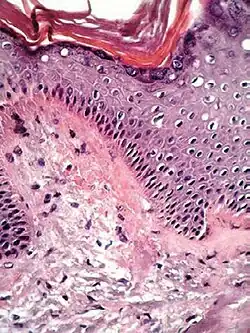

| Lichen planus | Irregular epidermal hyperplasia with a jagged "sawtooth" appearance, compact hyperkeratosis or orthokeratosis, foci of wedge-shaped hypergranulosis, basilar vacuolar degeneration, slight spongiosis in the spinous layer, and squamatization. The dermal papillae between the elongated rete ridges are frequently dome shaped. Necrotic keratinocytes can be observed in the basal layer of the epidermis and at the dermal-epidermal junction. Eosinophilic remnants of anucleate apoptotic basal cells may also be found in the dermis and are referred to as "colloid or civatte bodies". Whickham striae are usually seen in the areas of hypergranulosis. Vacuolar degeneration at the basal layer may be noted leading to focal subepidermal clefts (Max Joseph spaces). Squamatization occurs as a result of maturation and flattening of cells in the basal layer. It happens in areas of marked hypergranulosis with prominence of the sawtooth pattern of rete ridges. Wedge-shaped hypergranulosis can occur in the eccrine ducts (acrosyringia) or hair follicles (acrotrichia). In the hypertrophic subtype, the associated hyperkeratosis, parakeratosis, hypergranulosis, papillomatosis, acanthosis, and hyperplasia markedly increased with thicker collagen bundles forming in the dermis. Moreover, the rete ridges are more elongated and rounded as opposed to the typical sawtooth pattern. In atrophic LP, loss of the rete ridges and dermal fibrosis is prominent. In vesiculobullous LP, the disease progression is quicker. Hence, some of the distinctive features such as hyperkeratosis, hypergranulosis, or dense lymphocytic dermal-epidermal infiltrate may not be present. LP lesion may resolve with residual hyperpigmentation caused by a persistent increase in the number of melanophages in the papillary dermis.[9] | ![]() | ![]() |